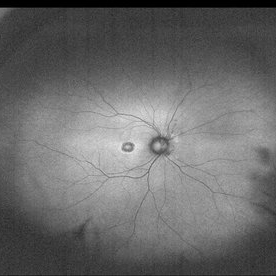

Choroideremia

35-year-old man VA 20/50 OU IOP 12mmHg.

Photographer: Andrea Elizabeth Arriola-LopezMD, MSc

Imaging device: OPTOS Dakota

Condition/keywords: choroideremia, retinal pigment epithelium